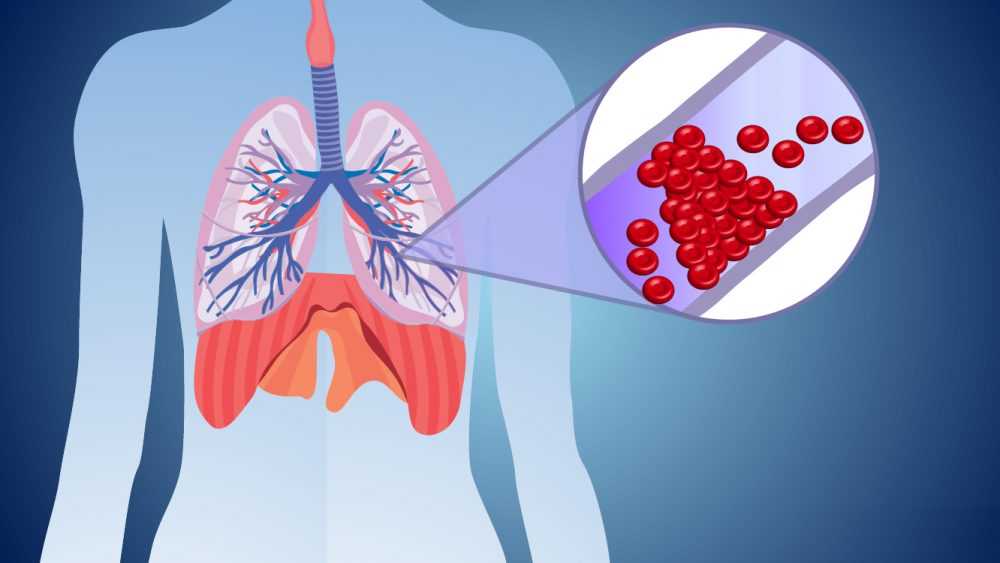

- Флебология